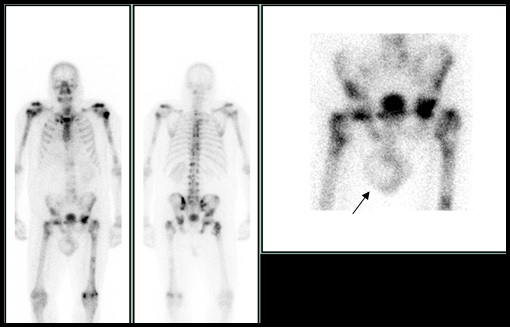

Se presenta el caso de un varón 57 años en seguimiento oncológico por adenocarcinoma de pulmón estadío IV con afectación hepática y ósea. El paciente se encontraba bajo tratamiento con quimioterapia desde hacía un año e inicio reciente de radioterapia sobre columna lumbar y pelvis (2 sesiones) por dolor errático, resistente a los analgésicos. Como seguimiento de la enfermedad metastásica ósea, se realiza gammagrafía con 814 MBq de Tc-99m-hidroxidifosfonato y adquisición de imágenes planares de cuerpo completo en proyección anterior y posterior (Fig.1). Se observaron numerosos depósitos patológicos del radiotrazador distribuidos en raquis, 3ª y 4ª uniones costo-vertebrales derechas, esternón, acromion izquierdo, húmeros, pelvis y fémures, en relación con infiltración metastásica. De manera incidental, se comprueba una zona de hipocaptación con halo hipercaptante en la proyección del testículo derecho, compatible con hidrocele escrotal.